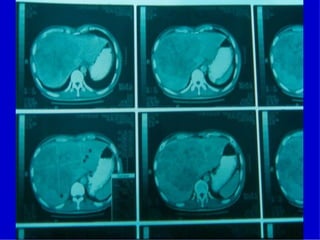

• Metástasis a ganglios linfáticos regionales 40-

70% casos

• Metástasis a distancia:

– hígado, pulmón, cavidad peritoneal, suprarrenales,

ovarios y hueso.